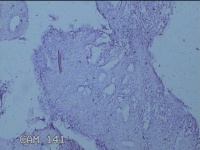

子宫腔内容物

性别

女

年龄

31岁

临床诊断

药流不全 子宫内膜炎待查

一般病史

药流术后1月。

标本名称

大体所见

灰白暗红色不规则碎组织1.5x1.3x0.3cm一堆,未发现明显的绒毛样组织。